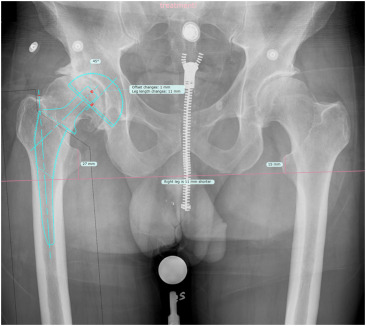

CASE REPORT One-Stage Primary TKA as the Treatment of Acute Septic Arthritis of the Native Osteoarthritic Knee: Report of 3 Cases and Review of Literature Key factors to success: patient selection, intraop technique, and comprehensive antibiotic plan https://t.co/FGUhUgGsJD